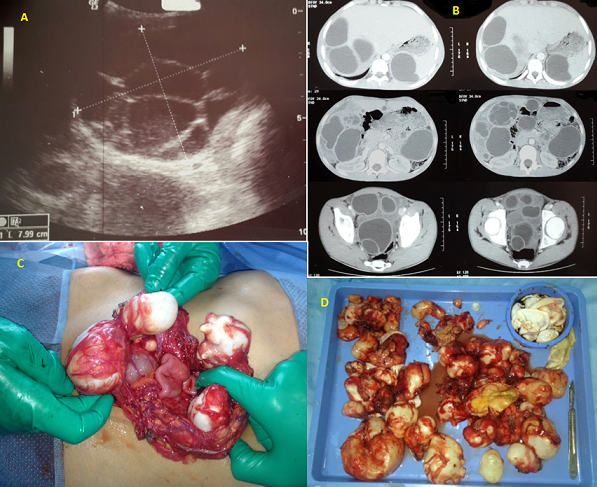

Hydatid cyst is a common disease in our country. The revelation by peritoneal hydatidosis is rare in children. We report the case of a 15 years old adolescent. History of the disease began a year by the occurrence of acute abdominal pain starting at the right hypochondrium; resolved with symptomatic treatment; no assessment was initially performed. The evolution was characterized by the recurrence of pain increasingly become intense with fever. Clinical examination revealed several abdominal masses spread to the whole abdomen measuring between 3 and 5 cm. Abdominal ultrasound showed peritoneal hydatidosis with splenic, hepatic, Douglas and inter-loop with multiple cysts classified type 1 (classifiations of Gharbi); only one cyst was multivesicular (A); the abdominal CT scan confirmed the same observation, indicated the location of cysts and the presence of a type 5 "calcified cyst" (B) . The blood cell counts does not shown any hypereosinophilia and CRP was elevated; a median laparotomy was performed. We proceeded with excision of peritoneal cyst; right hemi-omentectomy because the omentum contained several cysts ranging from 1 to 5 cm in size(C); Sterilizing the content of three hepatic cysts, extracting the germinal membrane; This same technique was realized for both splenic cysts; we have removed all 39 abdominal cavity cysts (D), a drainage was performed by three drains sub-hepatic; splenic lodge and Douglas; the post operative courses was simple; the patient was received albendazole at 10 mg/kg for 6 cycles of 15 days per month. Evolution was favorable.